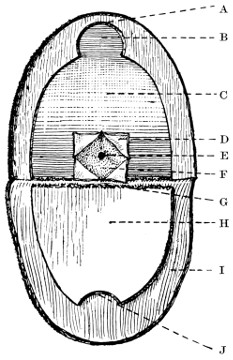

| 20. An occipital cephalocele | 33 |

| 22. An occipital cephalocele | 37 |

| 23. A depressed birth-fracture | 45 |

| 24 A and B. A case of depressed birth-fracture, before and after operation | 47 |

| 25. To illustrate the effects and position of a birth-hæmorrhage | 53 |

| 26. The author’s operation for Hydrocephalus internus | 64 |

| 27. The conversion of Hydrocephalus internus into cephalocele | 65 |

Fig. 20. An Occipital Cephalocele. (For further description, see text.)

1. Occipital cephaloceles—the commonest variety—occupy, anatomically, two positions (1) between the two lower segments of the occipital bone (inferior occipital cephaloceles), often involving the foramen magnum and sometimes complicated by a condition of cervical spina bifida, and (2) between the two upper segments of the occipital bone (superior occipital cephaloceles), occasionally involving the posterior fontanelle.

[34]

The tumour may possess a broad base or may be definitely pedunculated. In the former instance the gap in the bone may be of considerable size and the margins everted: in the latter case, the hole may be quite small.

The deformity is frequently associated with other congenital defects—hydrocephalus, microcephalus, spina bifida, hare lip, hernia, and talipes.

2. Sincipital cephaloceles occur next in order of frequency. The tumour projects between the nasal bones and the nasal process of the superior maxilla (naso-frontal), between the nasal process of the maxilla and the orbital plates of the ethmoid (naso-ethmoidal), or between the nasal bones (nasal).

Fig. 21. A Cephalocele over the Anterior Fontanelle.

(For further description, see text.)

3. More rarely, the tumour overlies the anterior or posterior fontanelle. A case of this nature is depicted in Fig. 21, the tumour, situated over the anterior fontanelle, bulging over the temporal and frontal regions to a remarkable extent.

4. Basal cephaloceles protrude through the cartilaginous base of the skull, either through the cribriform plate of the ethmoid, between the pre- and basi-sphenoid, or between the basi-sphenoid and basi-occiput, often projecting as a polypoid growth in the nose or naso-pharynx.

An interesting case of basal hernia was reported by von Mayer.[8] The child, 3 days old, was admitted with a tumour projecting into the right nostril, covered with mucous membrane, translucent, encrusted with scabs, pedunculated, and closely resembling a nasal polypus. The possibilities were fully recognized and all necessary precautions taken. The right half of the nose was turned back as a flap, the tumour isolated, ligatured, and removed. Death occurred after six weeks. An oval hole was found in the left half of the cribriform plate through which the dura mater projected and to the margins of which the membrane was firmly adherent. The pedicle contained ganglion-cells and nerve-fibres, whilst the parts removed showed, from without inwards, mucous membrane, dura mater, arachnoid, pia, and glial tissue.

Sincipital cephaloceles are usually quite small, but the occipital variety and those situated in[35] the region of the anterior fontanelle frequently attain a great size (see Figs. 20-22).

Fig. 22. An Occipital Cephalocele. (For further description, see text.)

It is not always possible to determine whether the tumour consists of a mere outward protrusion of membranes (meningocele), or whether brain-matter enters into the formation of the tumour (meningo-encephalocele). Fluctuation, translucency, and pulsation are all points to be investigated. All these features are, however, deceptive, and several cases are on record in which operative measures were carried out under the impression that the surgeon had to deal with a pure meningocele, and in which it was afterwards found that brain-matter formed the basis of the swelling.

When the tumour is large, the skin adherent, when no pedicle is present, when fluctuation and pulsation are absent, and when the tumour is of firm consistency, then it is practically certain that brain-matter shares largely in the formation of the tumour. On the[36] other hand, it is not unusual to find that the brain projects markedly outwards without resulting in any symptoms of brain irritation: fluctuation and pulsation are also not infallible signs, since the brain may occupy the base of the tumour, ‘corking-up’ the gap in the bone, or the brain may be so thinned by ventricular distension that a mere shell of cerebral matter lies beneath the scalp-covering.

Looking at the question from all points of view, it may be accepted that most cephaloceles contain either true brain-matter or the mixed epiblastic and mesoblastic elements described by Lyssenkow.

The following case serves to illustrate some of these facts:[9]—

The child was 3 months old, and presented a tumour, the size of an orange, situated between the occipital protuberance and the nape of the neck. The mass was pedunculated, the stalk being about the size of a four-shilling piece in diameter. It was soft, translucent, irreducible, and swelled up on coughing. An attempt at removal was carried out, and, after incising the outermost layers, three ounces of cerebro-spinal fluid escaped. A second tumour was then found occupying the base of the swelling. This was also punctured, more fluid escaping. Both sacs were cut away and the wound sewn up. Death occurred on the third day, preceded by convulsions, retraction of the head and neck, and high fever. The autopsy showed that the fontanelles were widely open, the anterior measuring 4 inches from side to side and 21⁄2 from before backwards. The bones of the vault were markedly thinned. In the subdural space there was a quantity of fluid, and the cerebral substance was soft and diffluent, the convolutions flattened, and the ventricles distended. There was a broad gap in the occipital bone, extending downwards into the foramen magnum, and in this situation the cerebellum had bulged backwards into the protruding mass. (See Fig. 22).